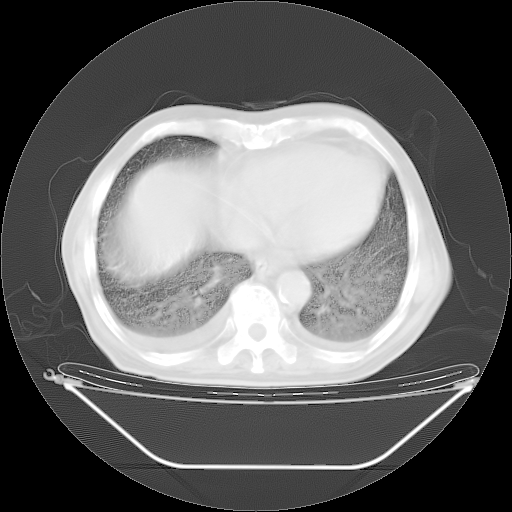

今天复查肺部CT,发现双肺广泛磨玻璃样改变。所以我把3月19日和5月9日相隔50天的肺部CT上传。请大家会诊。

5月9日肺部CT(在4月27日齐鲁医院肺部CT描述部分肺组织磨玻璃样改变,12天后肺组织广泛磨玻璃样改变)

2009年5月9日肺部CT